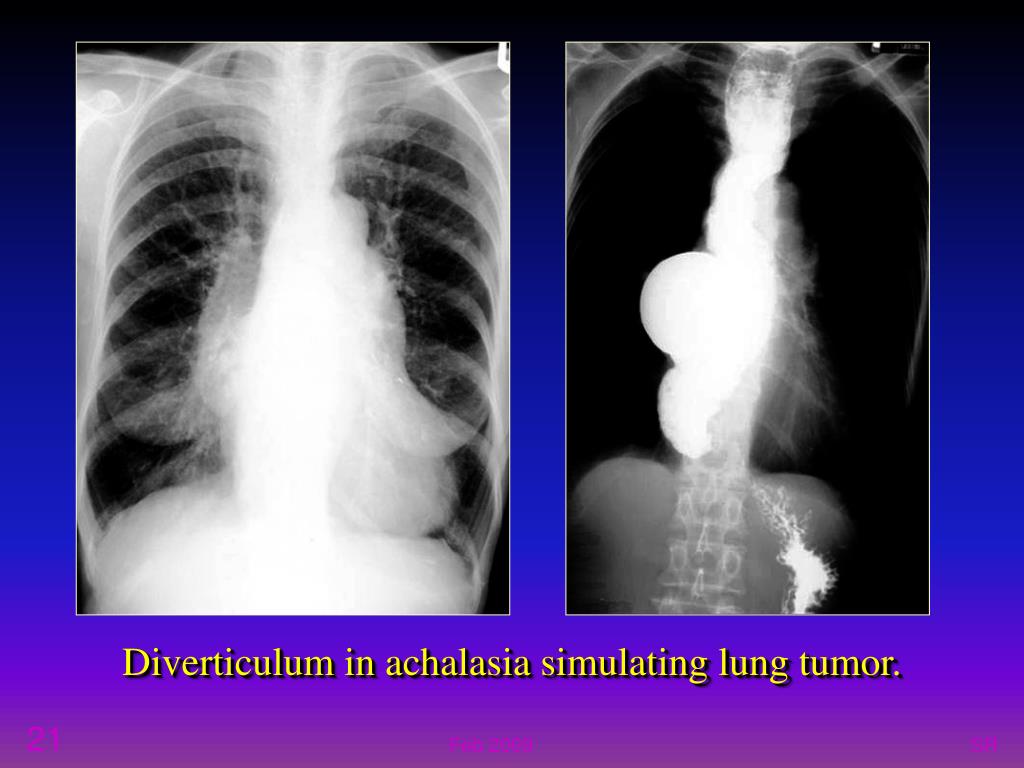

21. Diverticulum in achalasia simulating lung tumor. SR